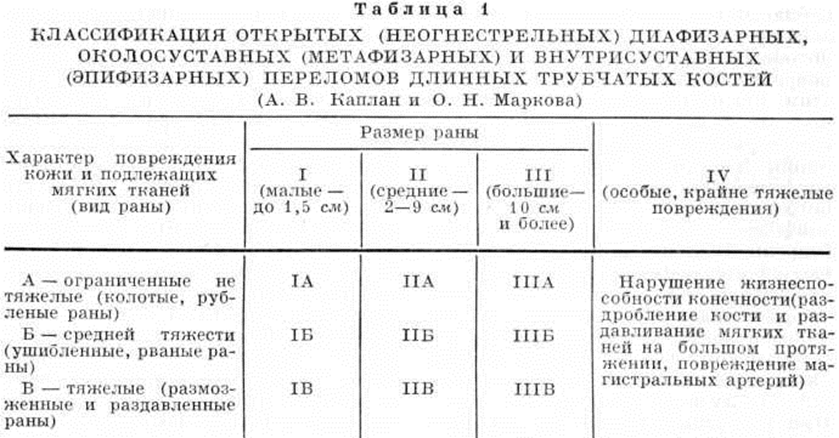

Предложено несколько классификаций открытых Переломы. Наиболее широкое распространение получила классификация А. В. Каплана и О. Н. Марковой, предложенная в 1967 год (таблица 1). Она учитывает обширность и характер повреждения кожи и всех подлежащих тканей, повреждение магистральных сосудов, локализацию и характер Переломы, то есть базируется на основных факторах, определяющих тяжесть и особенности открытого Переломы

Классификация позволяет не только уточнить диагноз открытого Переломы, но и более правильно установить показания к применению того или иного метода лечения, прогнозировать исход и проводить дифференциальный анализ исходов лечения в зависимости от тяжести открытого Переломы